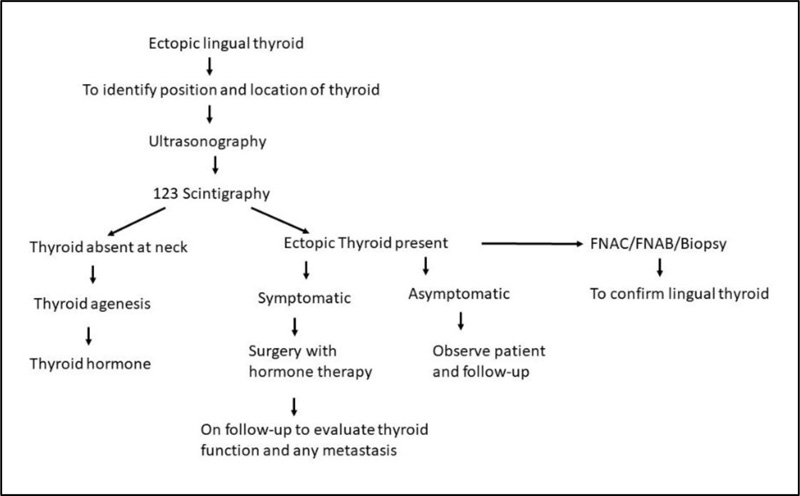

Figure, Ectopic thyroid] - StatPearls - NCBI Bookshelf Ectopic Thyroid - Endocrinesurgery.net.au Sites of ectopic thyroid localization along its descending pathway. | Download Scientific Diagram Ectopic thyroid tissue in the head and neck: a case series | BMC Research Notes | Full Text | Ectopic Thyroid